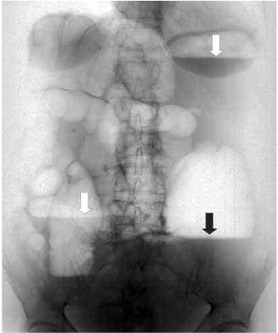

Онкологические заболевания. Опухоли толстого кишечника встречаются чаще, чем в тонком. На рентгене рак проявляется как дефект наполнения с четкой границей между новообразованием и здоровой слизистой оболочкой. Часто опухолевый процесс приводит к круговому сужению просвета кишечника, что называют признаком «яблочного огрызка».

Дивертикулярная болезнь — это состояние, при котором в стенке кишечника образуются мешковидные выпячивания через мышечный слой. На рентгене контуры дивертикула выглядят четкими и ровными. При воспалении границы становятся размытыми, а в выпячивании наблюдается длительная задержка контрастного вещества.

Рентгенологические признаки НЯК: утрата гаустрации, выпрямление, укорочение и сужение просвета кишечника, а также неравномерность рельефа слизистых оболочек из-за изъязвлений. Заболевание обычно начинается с поражения прямой кишки, после чего воспалительный процесс распространяется на другие сегменты толстой кишки, принимая форму левостороннего, субтотального или тотального колита.

Для болезни Крона характерны: прерывистые поражения, стриктуры, сужение и расширение просвета кишечника, рельеф «булыжной мостовой», свищи, псевдополипы и абсцессы в брюшной полости. В зависимости от локализации выделяют терминальный илеит, колит, илеоколит и изолированное поражение верхних отделов желудочно-кишечного тракта.